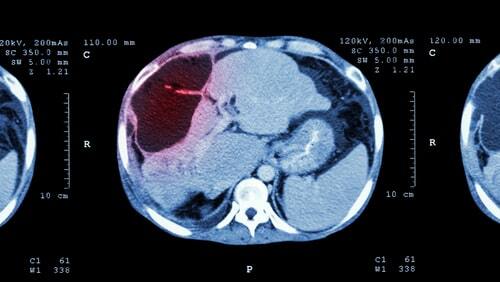

以显影剂的三相电脑扫瞄确诊可疑的肝脏肿瘤